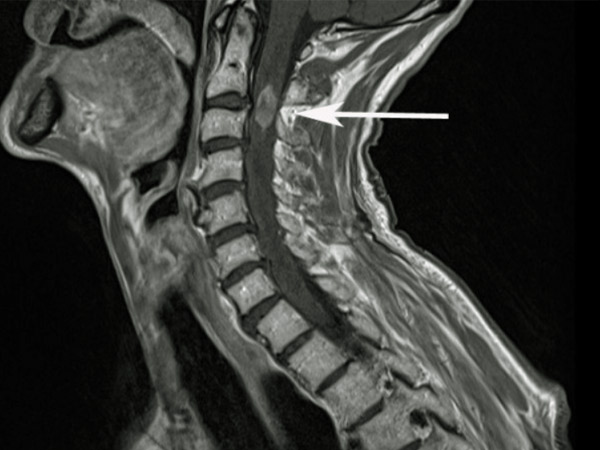

Kết quả chụp cộng hưởng từ cột sống cổ

Chụp cộng hưởng từ cột sống cổ được chỉ định khi trên lâm sàng có biểu hiện hội chứng chèn ép tủy, rễ thần kinh hay nghi ngờ có tổn thương khác kèm theo ở tủy sống. Khảo sát các lớp cắt theo mặt phẳng đứng dọc (sagittal), mặt phẳng nằm ngang (axial), mặt phẳng đứng ngang (coronal) cho ta nhiều thông tin về cột sống cổ của người bệnh: Vị trí, số lượng đĩa đệm thoát vị, tình trạng đĩa đệm còn hay không còn chứa nhân nhầy, tình trạng quá phát mỏ xương gây hẹp ống sống, hẹp lỗ ghép, tình trạng vôi hóa dây chằng dọc sau, dày dây chằng vàng gây hẹp ống sống, có phù tủy kèm theo không …

Phân bố tầng thoát vị đĩa đệm

Trong số 30 người bệnh thuộc nhóm nghiên đã được chụp cộng hưởng từ cột sống cổ trước mổ chúng tôi nhân thấy rằng:

Thoát vị đĩa đệm một tầng chiếm tỷ lệ 83,3%, Thoát vị đĩa đệm 2 tầng chiếm tỷ lệ 13,3%, thoát vị 3 tầng chiếm tỷ lệ 3,3% (biểu đồ 1). Nghiên cứu của Trương Thanh Tình và cộng sự [4] với 63 người bệnh thoát vị đĩa đệm cột sống cổ được phẫu thuật lối trước tai Bệnh viện Trường Đại Học Y Dược Thành Phố Hồ Chi Minh từ 1/2011 đến 12/2011 cho thấy phẫu thuật 1 tầng chiếm tỷ lệ 56%, 2 tầng 33%, 3 tầng chiếm 11%. Nghiên cứu của Hoàng Văn Chiến [2] trên 50 bệnh nhân đã phẫu thuật TVĐĐ cổ bằng phương pháp thay đĩa đệm nhân tạo có khớp từ tháng 1/2009 đến 3/2016 tại Bệnh viện Việt Đức thì số người bệnh thoát vị đĩa đệm 1 tầng chiếm tỷ lệ 76%, 2 tầng chiếm 24% và 3 tầng chiếm 4%. Nghiên cứu của Nguyễn Quốc Dũng [1] gồm 52 người bệnh được phẫu thuật thoát vị đĩa đệm cột sống cổ tại Bệnh viện Việt Đức từ 1/2003 đến 10/2004 thì số người bệnh thoát vị 1 tầng chiếm tỉ lệ 42,31%, 2 tầng chiếm 11,54%, 3 tầng chiếm 34,61%, 4 tầng chiếm 11,54%.

Vị trí đĩa đệm thoát vị trên phim cộng hưởng từ

Nghiên cứu 30 người bệnh với 36 đĩa đệm cột sống cổ thoát vị đã được phẫu thuật chúng tôi nhận thấy rằng: Thoát vị đĩa đệm C6-C7 gặp với tỷ lệ thấp nhất 2,7%, C3-C4 (16,7%), nhiều hơn là C4-C5 (38,9%), hay gặp nhất là thoát vị C5-C6 chiếm tỷ lệ 41,7% (bảng 3). Nguyễn Quốc Dũng [1] Nghiên cứu 52 người bệnh thoát vị đĩa đệm cột sống cổ thấy hay gặp nhất là thoát vị C5-C6 chiếm tỷ lệ 36,61%, C4-C5 (26,79%), C3-C4 (23,21%), C6-C7 (11,67%), ít gặp nhất là C7-T1 chiếm tỷ lệ 1,79%. Nguyễn Công Tô, Nguyễn Đình Hưng [5] nghiên cứu hay gặp nhất là thoát vị C5-C6 chiếm tỷ lệ 36,61%.

Một số hình thái thoát vị đĩa đệm cột sống cổ trên MRI

Trong nhóm nghiên cứu của chúng tôi 100% là thoát vị đĩa đệm ra sau, không gặp thoát vị ra trước hay thoát vị vào thân đốt sống. Giải thích cho điều này chúng tôi thấy rằng chỉ thoát vị đĩa đệm ra sau mới gây chèn ép vào tủy hay rễ thần kinh và gây lên các triệu chứng lâm sàng buộc người bệnh phải đến viện khám. Hình thái thoát vị hay gặp nhất là thoát vị trung tâm 61,1%, cạnh trung tâm 36,1%, thoát vị vào lỗ liên hợp 2,8% (bảng 3).

Nguyễn Quốc Dũng [1] nghiên cứu 52 người bệnh thoát vị đĩa đệm thấy thoát vị trung tâp chiếm 71,43%, cạnh trung tâm 25% và thoát vị vào lỗ liên hợp 3,57%. Hoàng Văn Chiến [2] nghiên cứu thì tỷ lệ thoát vị trung tâm là 45,45%, cạnh trung tâm 33,33%, thoát vị liên quan đến lỗ liên hợp 21,22%.

Thoát vị đĩa đệm cột sống cổ thể trung tâm và cạnh trung tâm chiếm tỷ lệ cao nhất, điều đó hoàn toàn phù hợp với đặc điểm giải phẫu của cột sống cổ. Do các sợi dây chằng dọc sau phân bố đồng đều ở mặt trước ống sống cổ mà không tập chung phân bố ở giữa, đồng thời vòng sợi đĩa đệm ở phía sau yếu hơn nửa phía trước đó là nguyên nhân chính là tăng tỷ lệ thoát vị đĩa đệm trung tâm và cạnh trung tâm. Do đặc điểm của gờ xương quanh bề mặt của thân đốt sống, đặc điểm khớp luschka cũng góp phần làm cho tỷ lệ thoát vị vào lỗ ghép ít gặp hơn.